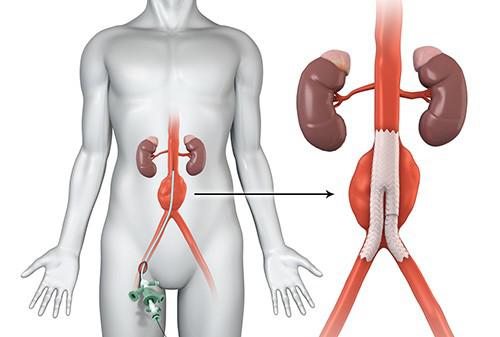

Overview

Package includes:

Days in hospital : 4 to 5 Days (For patient and one attendant)

Days in hotel : 7 Days (For patient and one attendant)

Room type in hospital : Shared

Room type in hotel : Private

Hotel category: Standard

Value added benefits of the Renal Angioplasty:

Ø Doctor consultation charges

Ø Lab tests and diagnostic charges

Ø Room charges inside hospital during the procedure

Ø Surgeon Fee

Ø Nursing charges

Ø Hospital surgery suite charges

Ø Anesthesia charges

Ø Routine medicines and routine consumables (bandages, dressings etc.)

Ø Food and Beverages inside hospital stay for patient and one attendant.

Extra benefits:

ü Interpreter

ü Visa assistance

Ø Site tourism of the city

Ø Follow up with the doctor

Ø Airport pick up and drop

Ø Free online consultation with the doctor

Ø Priority appointments with the doctor

Ø Room upgrade from sharing to private